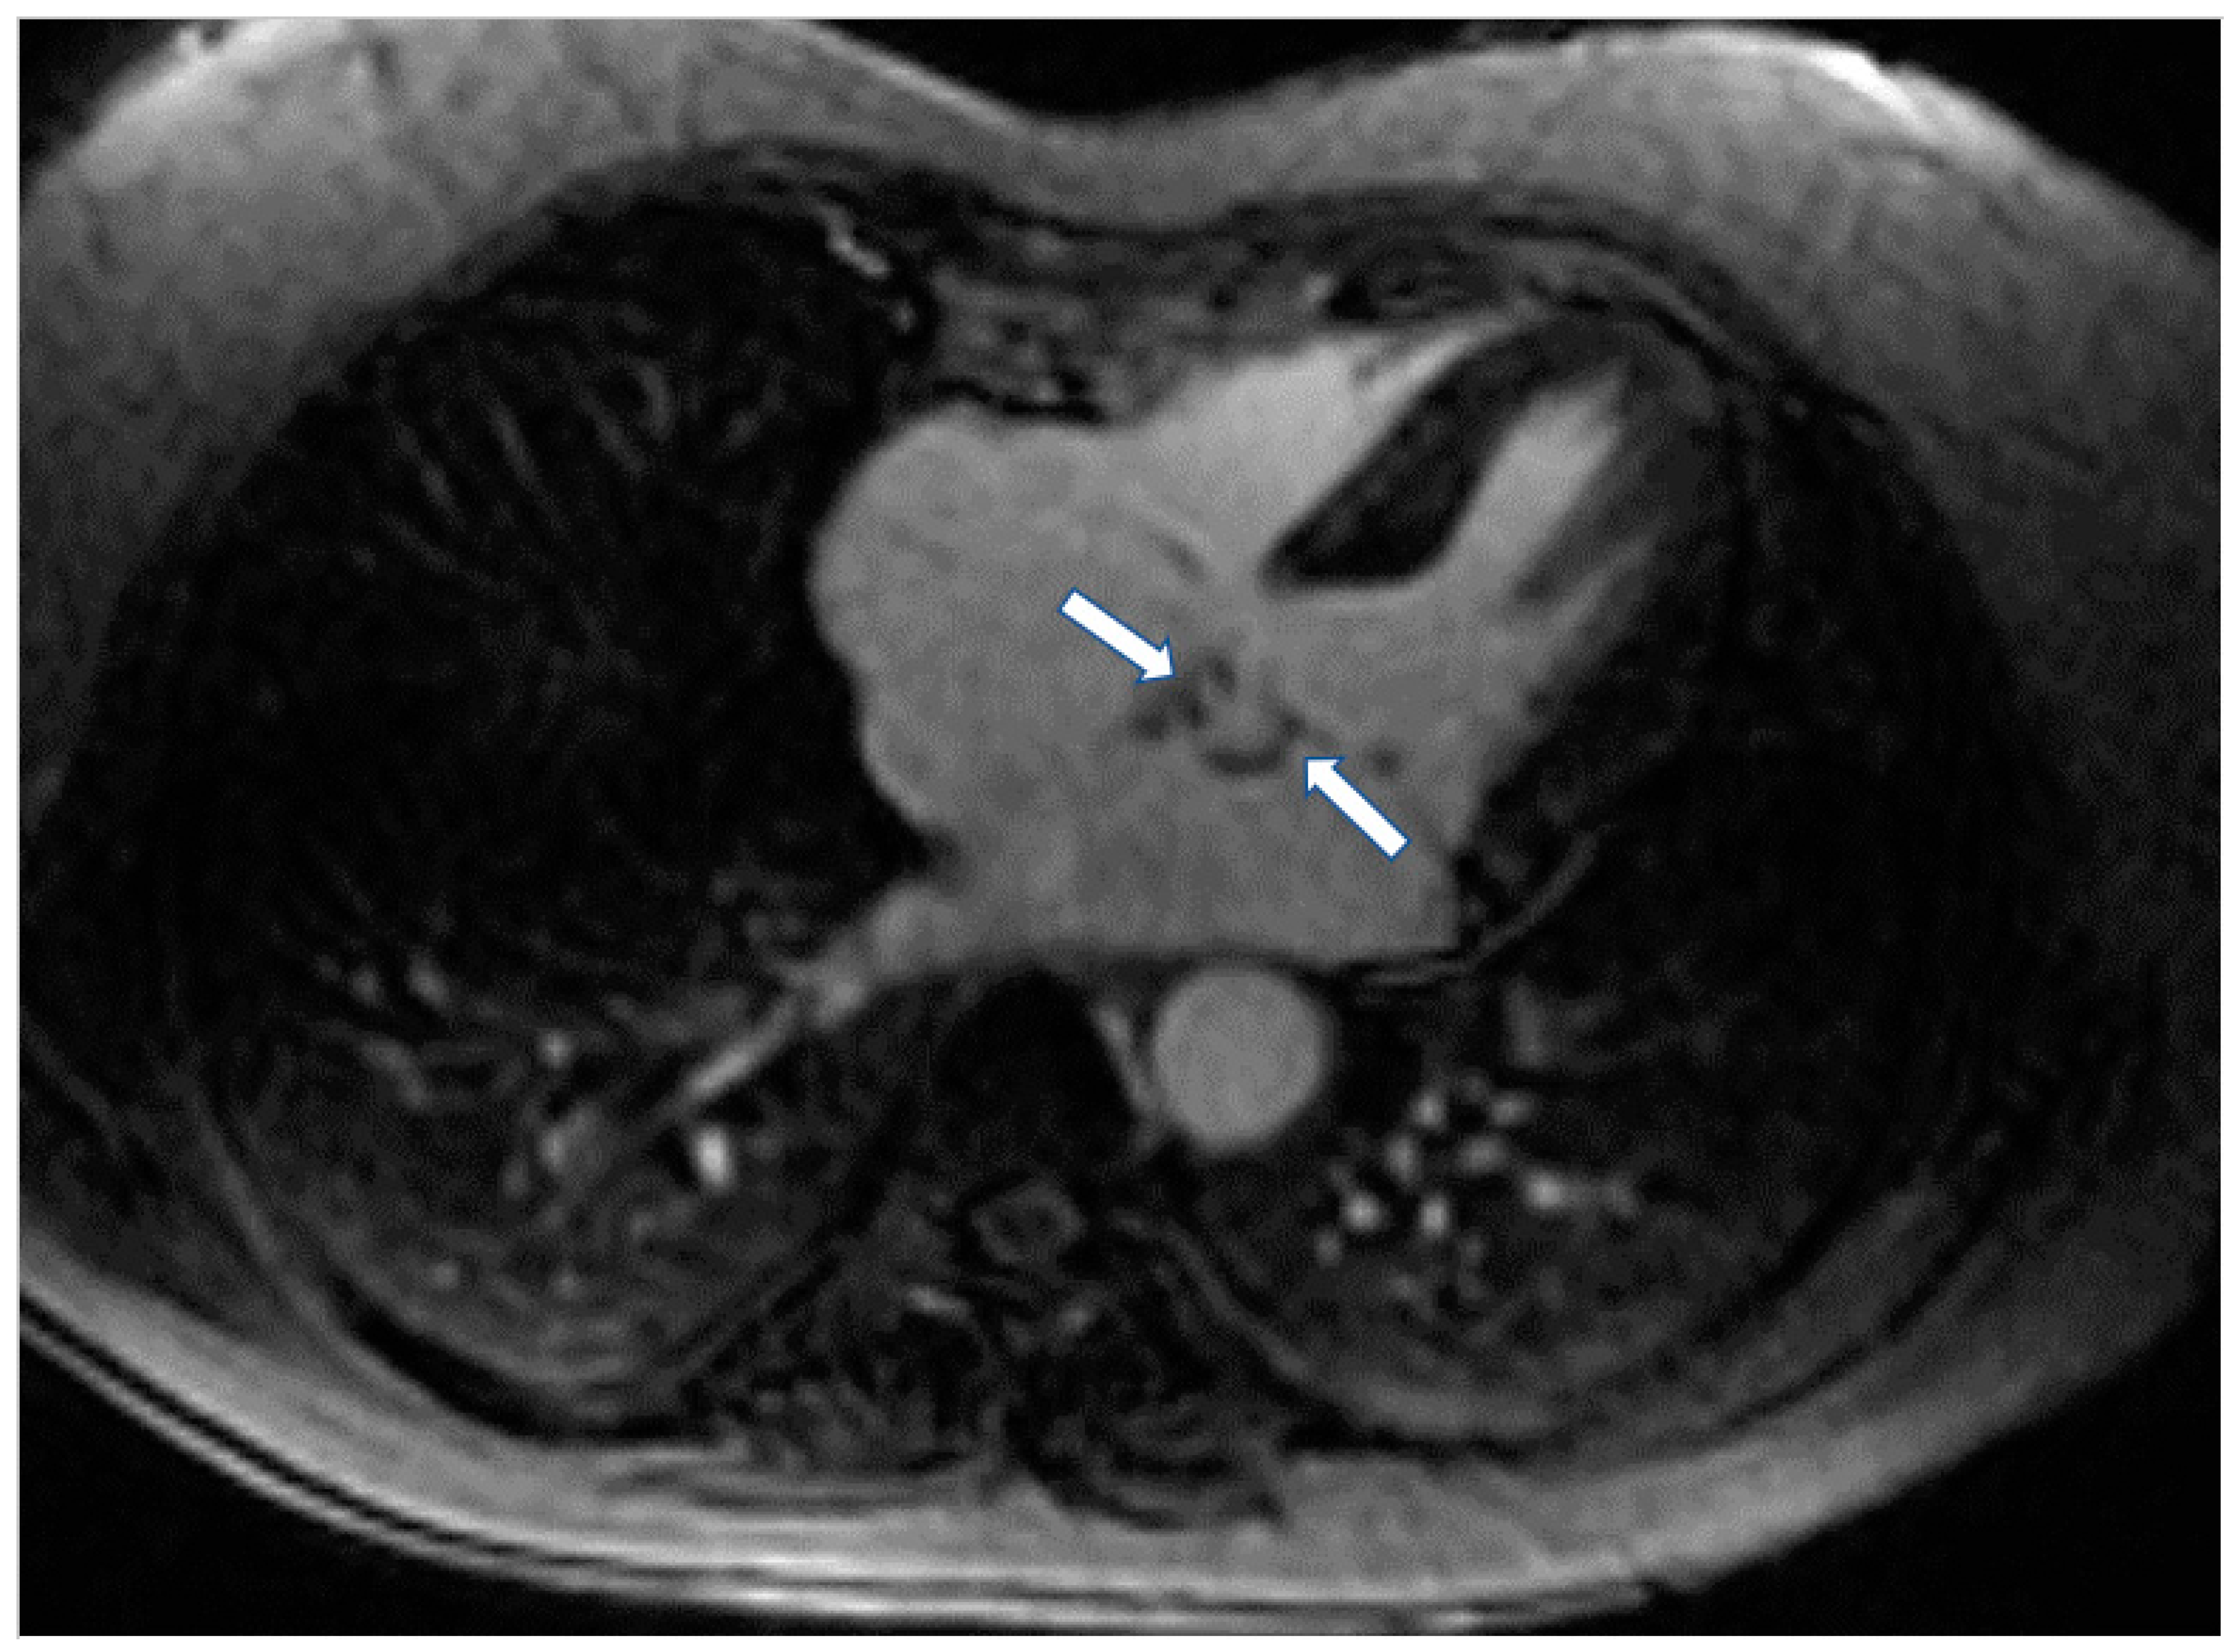

Figure 3.

Short axis LGE image showing diffuse subendocardial fibrosis (arrows) in a patient with Churg–Strauss vasculitis.